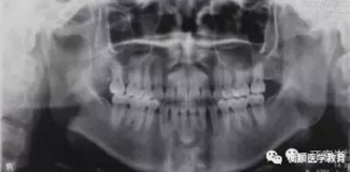

圖3 治療前曲面體層片